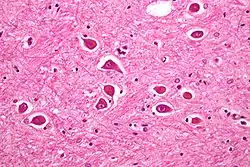

Micrograph of Alzheimer type II astrocytes, as may be seen in hepatic encephalopathy | |

There are various explanations why liver dysfunction or portosystemic shunting might lead to encephalopathy. In healthy subjects, nitrogen-containing compounds from the intestine, generated by gut bacteria from food, are transported by the portal vein to the liver, where 80–90% are metabolised through the urea cycle and/or excreted immediately. This process is impaired in all subtypes of hepatic encephalopathy, either because the hepatocytes (liver cells) are incapable of metabolising the waste products or because portal venous blood bypasses the liver through collateral circulation or a medically constructed shunt. Nitrogenous waste products accumulate in the systemic circulation (hence the older term "portosystemic encephalopathy"). The most important waste product is ammonia (NH3). This small molecule crosses the blood–brain barrier and is absorbed and metabolised by the astrocytes, a population of cells in the brain that constitutes 30% of the cerebral cortex. Astrocytes use ammonia when synthesising glutamine from glutamate. The increased levels of glutamine lead to an increase in osmotic pressure in the astrocytes, which become swollen. There is increased activity of the inhibitory γ-aminobutyric acid (GABA) system and the energy supply to other brain cells is decreased. This can be thought of as an example of brain edema of the "cytotoxic" type.[14]